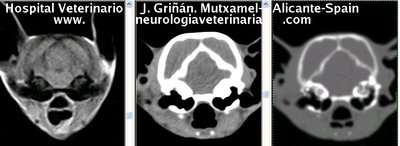

Se muestran cortes transversales de Resonancia Magnética (imagen a la izqda del lector), TC contrastado para tejidos blandos (imagen del centro) y TC contrastado para tejidos duros (imagen de la derecha del lector).

Nótese como la Resonancia supera al TC en el contraste de tejidos blandos (encéfalo y médula espinal) y en el de líquidos (ojo y líquido cefalorraquídeo), mientras que el TC supera a la resonancia en el contraste de tejidos duros (hueso) y aire (senos, cavidad nasal y bullas)

Cortes transversales a nivel de la articulación atlanto-occipital. Nótense la herniación del cerebelo por el agujero magno.